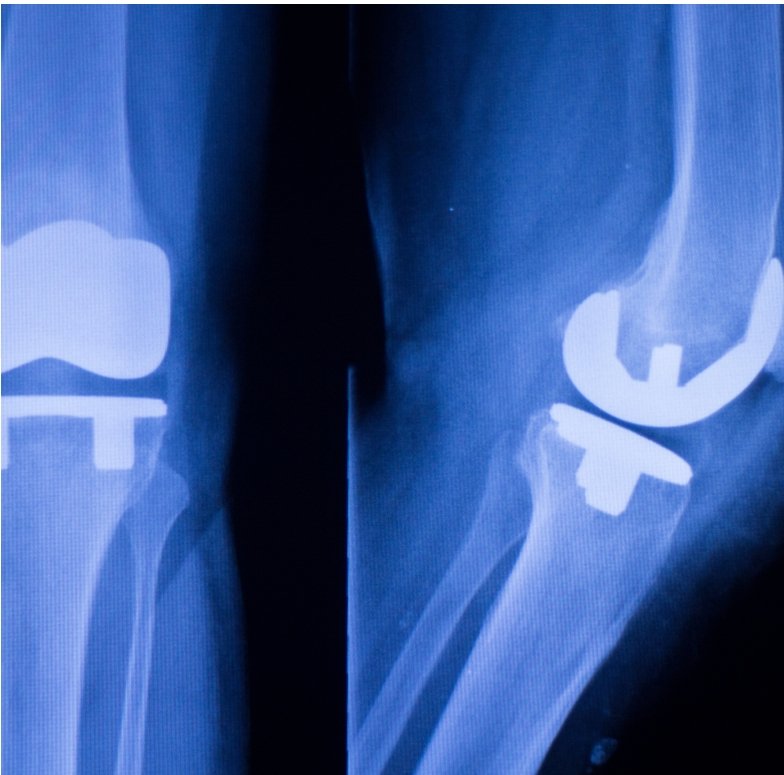

Knee & Hip Replacement Surgeries